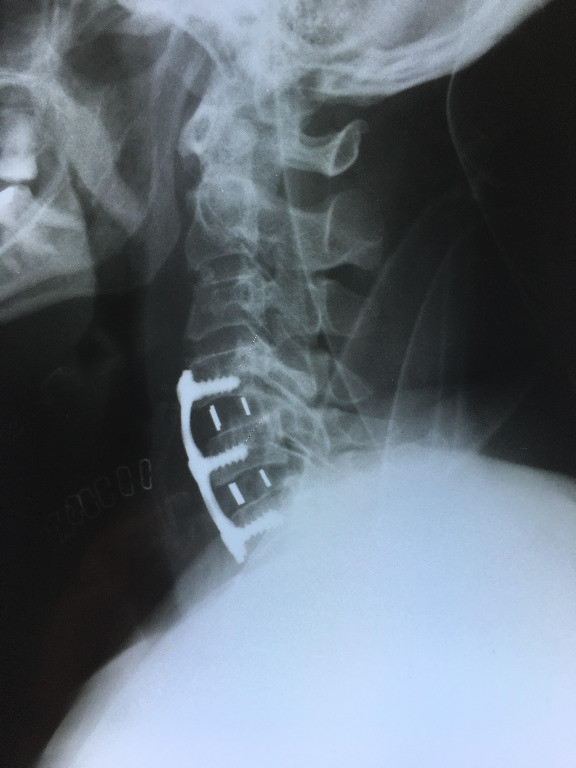

Artroplastía lumbar y prótesis de columna

Envíado por Dr. Hugo Enrique Castro Cordero